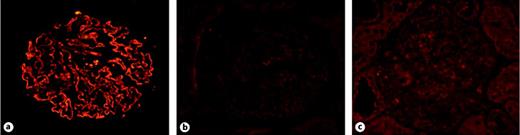

Renal PLA2R detection and the co-staining of PLA2R and HBsAg in the glomeruli were performed on paraffin-embedded renal biopsy samples. Citrate buffer of pH 6.0 and microwaving at 100% power for 8 min were used for antigen retrieval. Three percent bovine serum albumin was used for blocking. The anti-PLA2R-Ab (Sigma, HPA012657) was diluted at 1:500 and incubated overnight at 4°C. The secondary antibody was a fluorescein Cy3-conjugated donkey anti-rabbit IgG antibody (Jackson, 711-165-152) and diluted at 1:200. Positive PLA2R was characterized as granular staining along the capillary loops and scaled from 0 to 3+ (fig. 1). The anti-HBsAg antibody (Gene Tech, GT202429) was diluted at 1:50 and co-incubated with anti-PLA2R-Ab overnight at 4°C, and then detected by an Alexa-green G488-conjugated donkey anti-mouse IgG antibody (Jackson, 715-545-150). Negative control (secondary antibody only) was used in every case to exclude the cross-reactions between secondary antibody and human IgG.

The staining of PLA2R in the kidney. Renal PLA2R was positive by granular distribution along the glomerular capillary wall in MN patients (a), but negative in these slides added secondary antibody only (b) and in healthy control (c). (Original magnification ×400.)